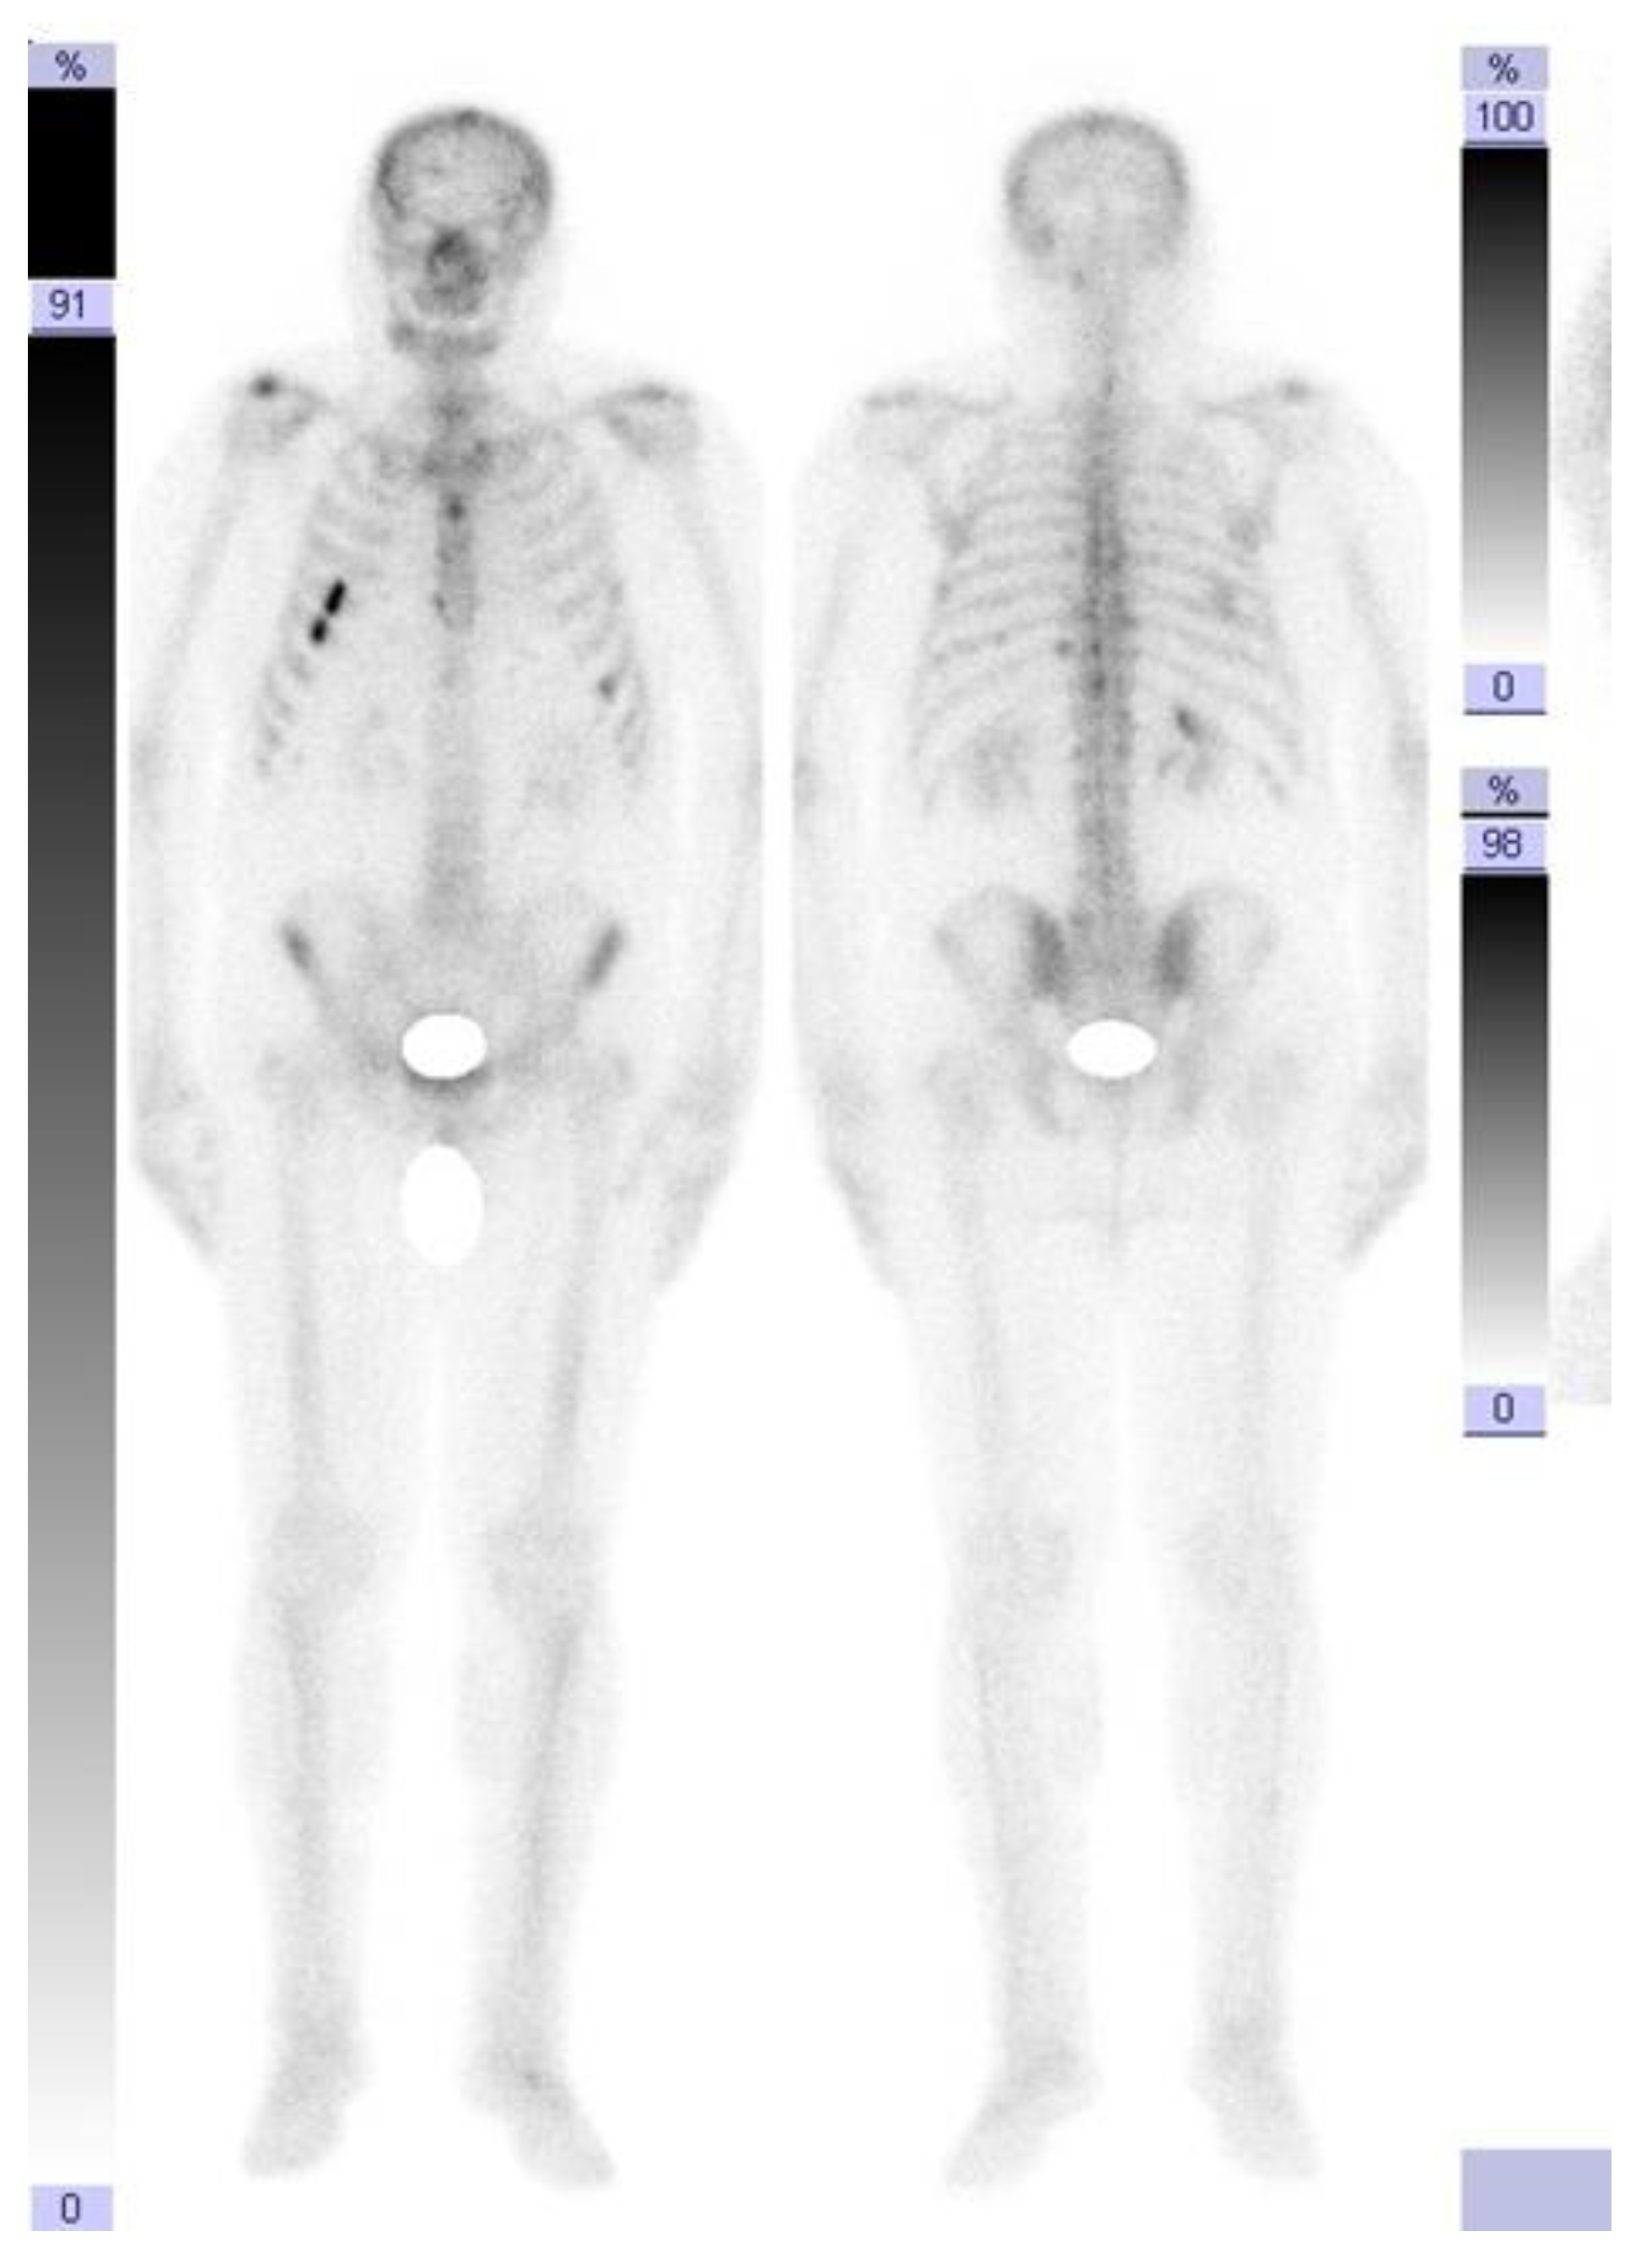

Treatment with abiraterone (an androgen biosynthesis inhibitor) + prednisone + Lh-Rh analog was initiated, a treatment indicated for castration-resistant prostate cancer, which progressed after the docetaxel-based therapy. After 9 months of treatment, in April 2021, the PSA value was 66 ng/mL, and a new imaging evaluation through computed tomography revealed a prostate with increased dimensions (axial diameters: 48/45 mm) and the presence of a medial lobe and a diffusely non-homogenous structure. The seminal vesicles presented no significant densitometry particularities. The liver had a non-homogenous structure, with the presence of a hypocapturing mass with axial diameters of 28/26 mm located at the subscapular region at the border of segments VI and VII, suspected from the CT to be a secondary-type lesion.

The presence of intra-aortocaval and middle lower lumboaortic retroperitoneal lymph nodes with maximum axial diameters of 17/11 mm was observed. There were no ascites at the abdominal-pelvic level. No inguinal adenopathy or hydro-aerial distensions in the intestinal abdominal-pelvic area were observed. Multiple focal osteocondensed, sternocostal, clavicular, scapular, and thoraco-lumbar vertebral lesions were observed, as well as lesions at the level of the bony pelvis with an appearance suggestive of secondary bone determinations; practically, this represented a significant progression of secondary bone determinations (Figure 2 and Figure 3).

Figure 2. Computed tomography (April 2021): liver with non-homogenous structure, with the presence of a hypocapturing mass with axial diameters of 28/26 mm. Middle and lower interaorticocaval and lumboaortic retroperitoneal lymph nodes with maximal axial diameters of 17/11 mm.